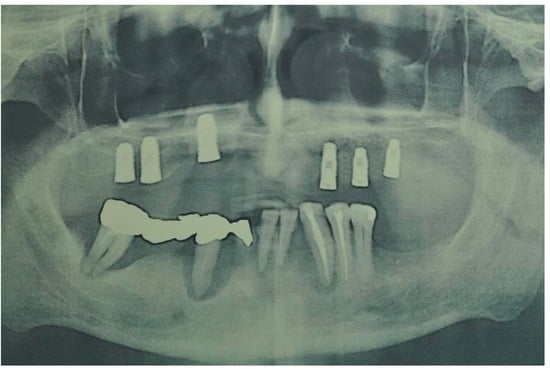

| Flanagan D. et al. [23] | J Oral Implantol | 2015 | clinical and radiographic: full-mouth radiographic series, panoramic and a bimaxillary cone beam computerized scan and mounted study casts | -One patient | Subject of 34 yo male; severely carious teeth and associated chronic abscesses (kidney transplant delayed) Comorbidities: IgA nephropathy, tabagism, hypertension and secondary hyperparathyroidism. Hemodialysis three times weekly. Ph. Therapy: Nephrocaps vitamin (B) supplement, amlodepine, besylate, cinacalcet, metoprolol, paroxetine. Bilateral compound ulnar and radial fractures, 2 blood transfusions. | Successfully treated with dental implant-supported fixed prostheses: fixed bimaxillary porcelain fused to metal implant-supported complete dentures |

| Flanagan D. et al. [23] | J Oral Implantol | 2015 | -Implant treatment for patients with IgA nephropathy (secondary hyperparathyroidism and osteodystrophy) may be successful. -Appropriate calcium therapy is important serum calcium to prevent inappropriate bone remodeling | 2 years | Long-term dialysis patient with end-stage renal disease (ESRD)also referred to as chronic kidney disease (CKD) due to IgA nephropathy complicated by severe secondary hyperparathyroidism and renal osteodystrophy | |